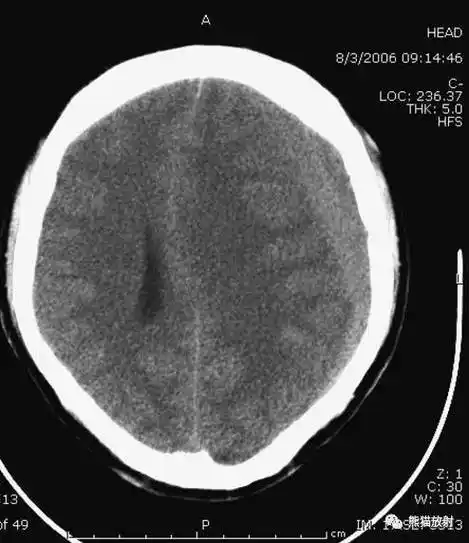

值班必备 | 急诊颅脑ct常见的八种疾病